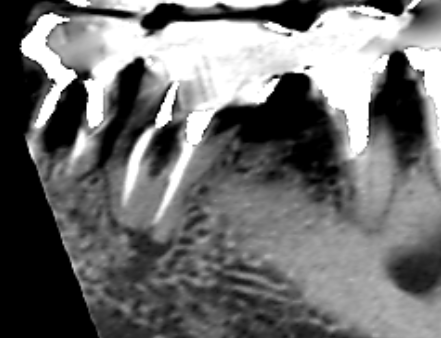

下顎第一大臼歯の近心根の冠状断のCT画像です。

矢印の下顎第一大臼歯の近心根の先に膿の影がみられます。近心根の根管は一本だけでした。